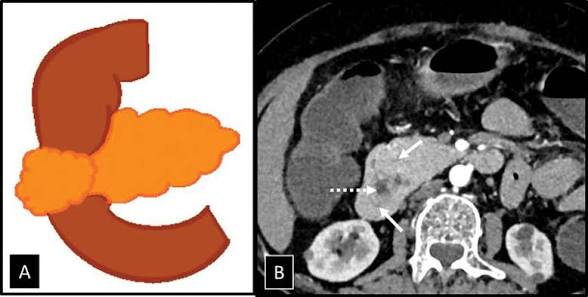

Annular pankreas, normal pankreas dokusunun duodenumun 2. kısmını (pars descendens) halka şeklinde sarmasıdır.

Annular pankreasda ise ikiye bölünmüş ventral bud, Duodenumun etrafını sarar.

Eğer ventral pankreas iki loba ayrılırsa, bir lob dorsal uzantıya ek olarak daha da ventral yönde uzanırsa veya ventral lob sabit kalırsa, duodenumun inen kısmının etrafında bir halka oluşarak lümenini daraltabilir . Tıkanıklığın derecesine bağlı olarak, bu durum anne karnında, yenidoğanlarda veya yaşamın üçüncü veya dördüncü on yılında belirgin hale gelebilir, ancak tamamen asemptomatik de kalabilir. Tanı ultrason , ERCP ve BT kullanılarak konulur . Tipik semptomlar arasında (muhtemelen safra içeren) yemek sonrası kusma ve şişkinlik bulunur.

Tipik olarak Duodenum çevresinde pankreas halkası tespit edilir.

Embriyolojik Rotasyon ve Füzyon Kusuru; Normal gelişimde ventral tomurcuk, duodenumun rotasyonu ile dorsal tomurcuğun arkasına geçer ve füzyon gerçekleşir. Sizin de belirttiğiniz gibi, ventral tomurcuğun iki loba ayrılması veya göç sırasındaki bir hata, duodenumun 2. kıtasını (descending part) bir yüzük gibi saran pankreas dokusuna yol açar.